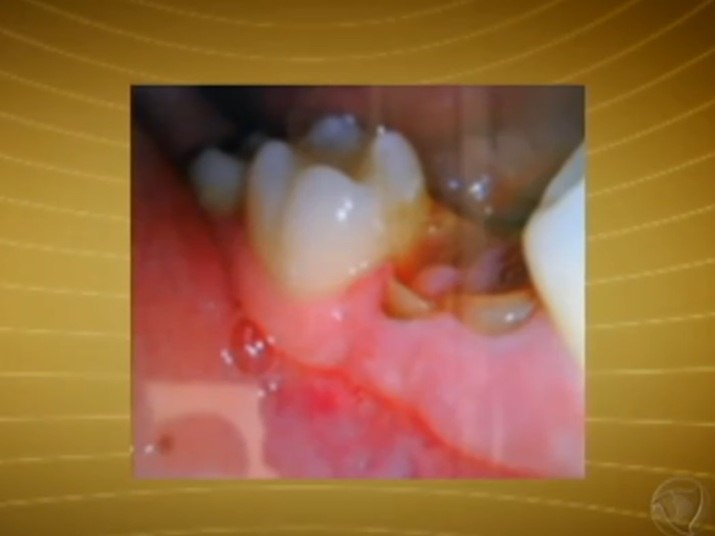

AnteriorEndocardite é uma infecção no endocárdio, revestimento interno do coração. Normalmente a doença acontece quando uma bactéria ou germes de outra parte do corpo, como os da boca, se espalham pelo sistema sanguíneo se ligando a áreas afetadas do coração. A endocardite é incomum em pessoas com coração saudávelNo R7 Play você pode assistir ao Fala Brasil na

Endocardite é uma infecção no endocárdio, revestimento interno do coração. Normalmente a doença acontece quando uma bactéria ou germes de outra parte do corpo, como os da boca, se espalham pelo sistema sanguíneo se ligando a áreas afetadas do coração. A endocardite é incomum em pessoas com coração saudável

A endocardite é responsável por uma alta morbidade e por significativas tazas de mortalidade

.Em torno de 20% dos doentes não sobrevivem.